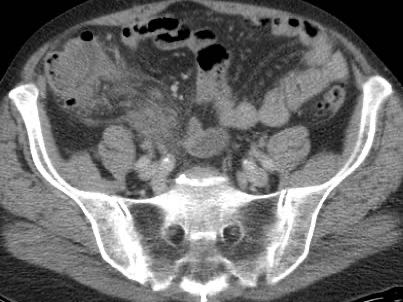

Ở người phụ nữ 56 tuổi này với CRP 180, siêu âm phát hiện dịch trong phúc mạc đục (*) và có thể thấy ruột thừa viêm với sỏi phân (mũi tên).

CT xác nhận hai sỏi phân ở hố chậu phải với hình ảnh khí bất thường, nghi ngờ viêm ruột thừa thủng.

Chọc hút dưới hướng dẫn siêu âm xác nhận dịch mủ.

Phẫu thuật cấp cứu phát hiện viêm ruột thừa thủng với nhiễm bẩn mủ bốn góc phần tư ổ bụng.